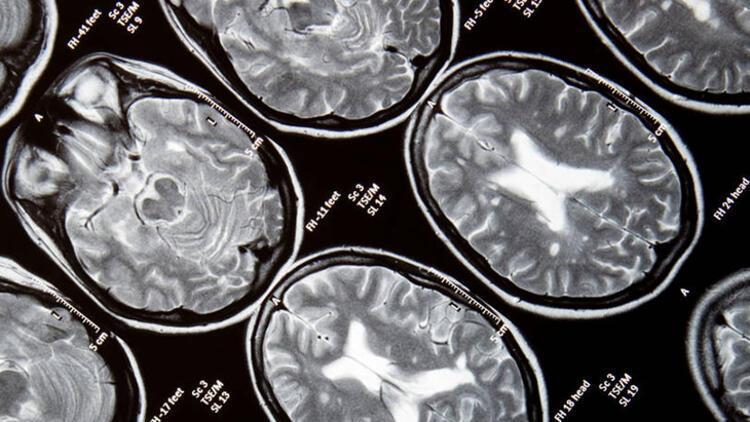

MS’in tek bir tanısal yöntemi yoktur. Genellikle hastanın öyküsü, nörolojik muayene bulguları, beyin ve omurilik MR sonuçları, bazı durumlarda belden sıvı alınarak bakılan beyin ve omurilik sıvı bulguları ve bazen de elektrofizyolojik testler bir arada incelenerek tanı konur.